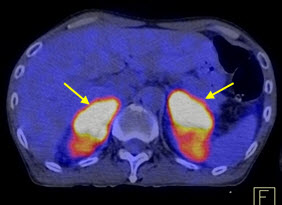

Hình 5. Bệnh nhân Nguyễn X.T., nam, 58 tuổi. Chẩn đoán: U lympho ác tính không Hodgkin, giải phẫu bệnh: WF6. Hình PET cho thấy tổn thương ở phổi, hạch, xương, tuyến thượng thận hai bên (mũi tên). Hình CT và PET/CT cho thấy tổn thương tăng hấp thu FDG tại vị trí tuyến thượng thận hai bên (mũi tên), max SUV=11,34.

Hình 6. Bệnh nhân Vũ D.L., nam, 56 tuổi. Chẩn đoán: Non Hodgkin Lymphoma , GPB: WF7.Hình PET/CT trước và sau điều trị. Trước điều trị bệnh nhân có tổn thương hạch tại rất nhiều vị trí trong cơ thể: hạch cổ, hạch trung thất, hạch ổ bụng. Sau điều trị hóa chất 6 đợt, bệnh nhân được chụp PET/CT để đánh giá đáp ứng điều trị thấy các hạch hoàn toàn biến mất. Bệnh đáp ứng hoàn toàn.